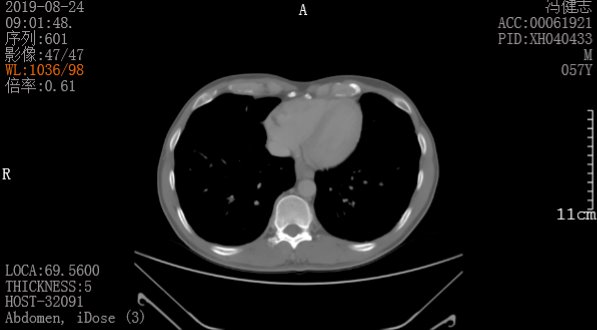

胸腹部CT:

1、右中肺、双下肺少量炎症合并支气管扩张。

2、双上肺、右下肺背段继发性肺结核,病灶以纤维增殖灶为主,合并支气管扩张。

3、甲状腺右叶低密度灶,性质待定,结节性甲状腺肿?

4、肝脏稍低密度灶、腹膜后多发淋巴结肿大,性质待定,建议腹部CT平扫及增强扫描检查。